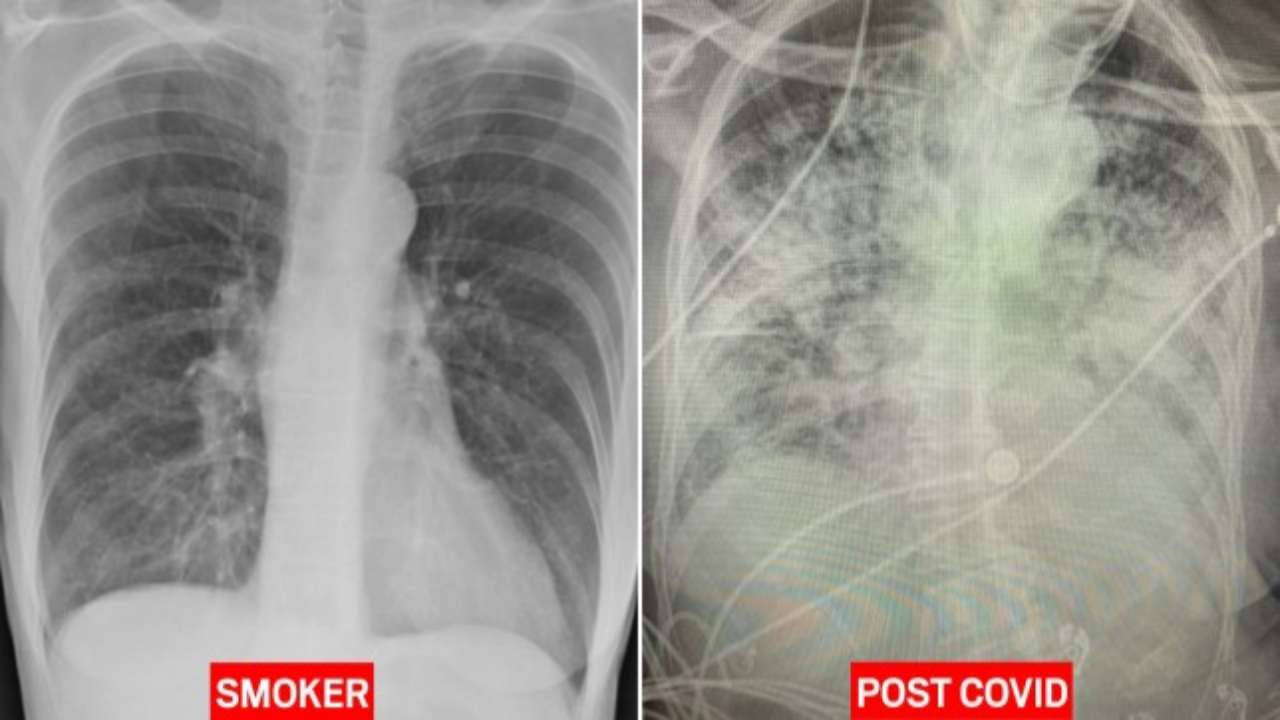

Covid, dottoressa lancia l’allarme: “Danni ai polmoni più gravi nei malati covid che nei fumatori”

I don’t know who needs to hear this, but “post-Covid” lungs look worse than ANY type of terrible smoker’s lungs we’ve ever seen.

And they collapse. And they clot off.

And the shortness of breath lingers on… & on… & on.

Chiaramente si tratta di studi preliminari e non vi è assoluta certezza su quanto tempo possano perdurare i danni polmonari causati dal Covid-19. Tuttavia nelle scorse ore una dottoressa britannica ha condiviso un allarme che non fa dormire sonni tranquilli. Il medico, una radiologa inglese, ha spiegato che dall’osservazione delle lastre polmonari nei pazienti guariti dal Covid-19 ha notato la presenza di danni molto gravi che potrebbe causare in futuro problematiche serie.

In pratica i polmoni delle persone che hanno avuto il Covid-19 risultano completamente bianchi, segno della presenza di danni e della difficoltà di incameramento dell’ossigeno da parte degli organi. Per fare capire quanto sia allarmante la condizione, la dottoressa Bankhead-Kendall ha pubblicato anche la lastra di un fumatore, mostrando come i polmoni di quest’ultimo presentassero ampi spazi scuri, segnale di un’abbondante presenza di ossigeno.

Nel commentare le immagini a raggi x, la dottoressa spiega: “Non so chi ha il bisogno di sentirsi dire questo, ma i polmoni ‘Post Covid’ appaiono peggio di quelli di qualsiasi fumatore accanito che abbiamo mai visto. E questi collassano. E questo coagulano. Ed il respiro corto perdura ancora, ancora e ancora”. Il medico ha successivamente aggiunto: “Ci sono ancora persone che dicono ‘Sto ben non ho alcuni tipo di problema’, poi gli fa una radiografia polmonare e ti trovi davanti ad una pessima radiografia”.